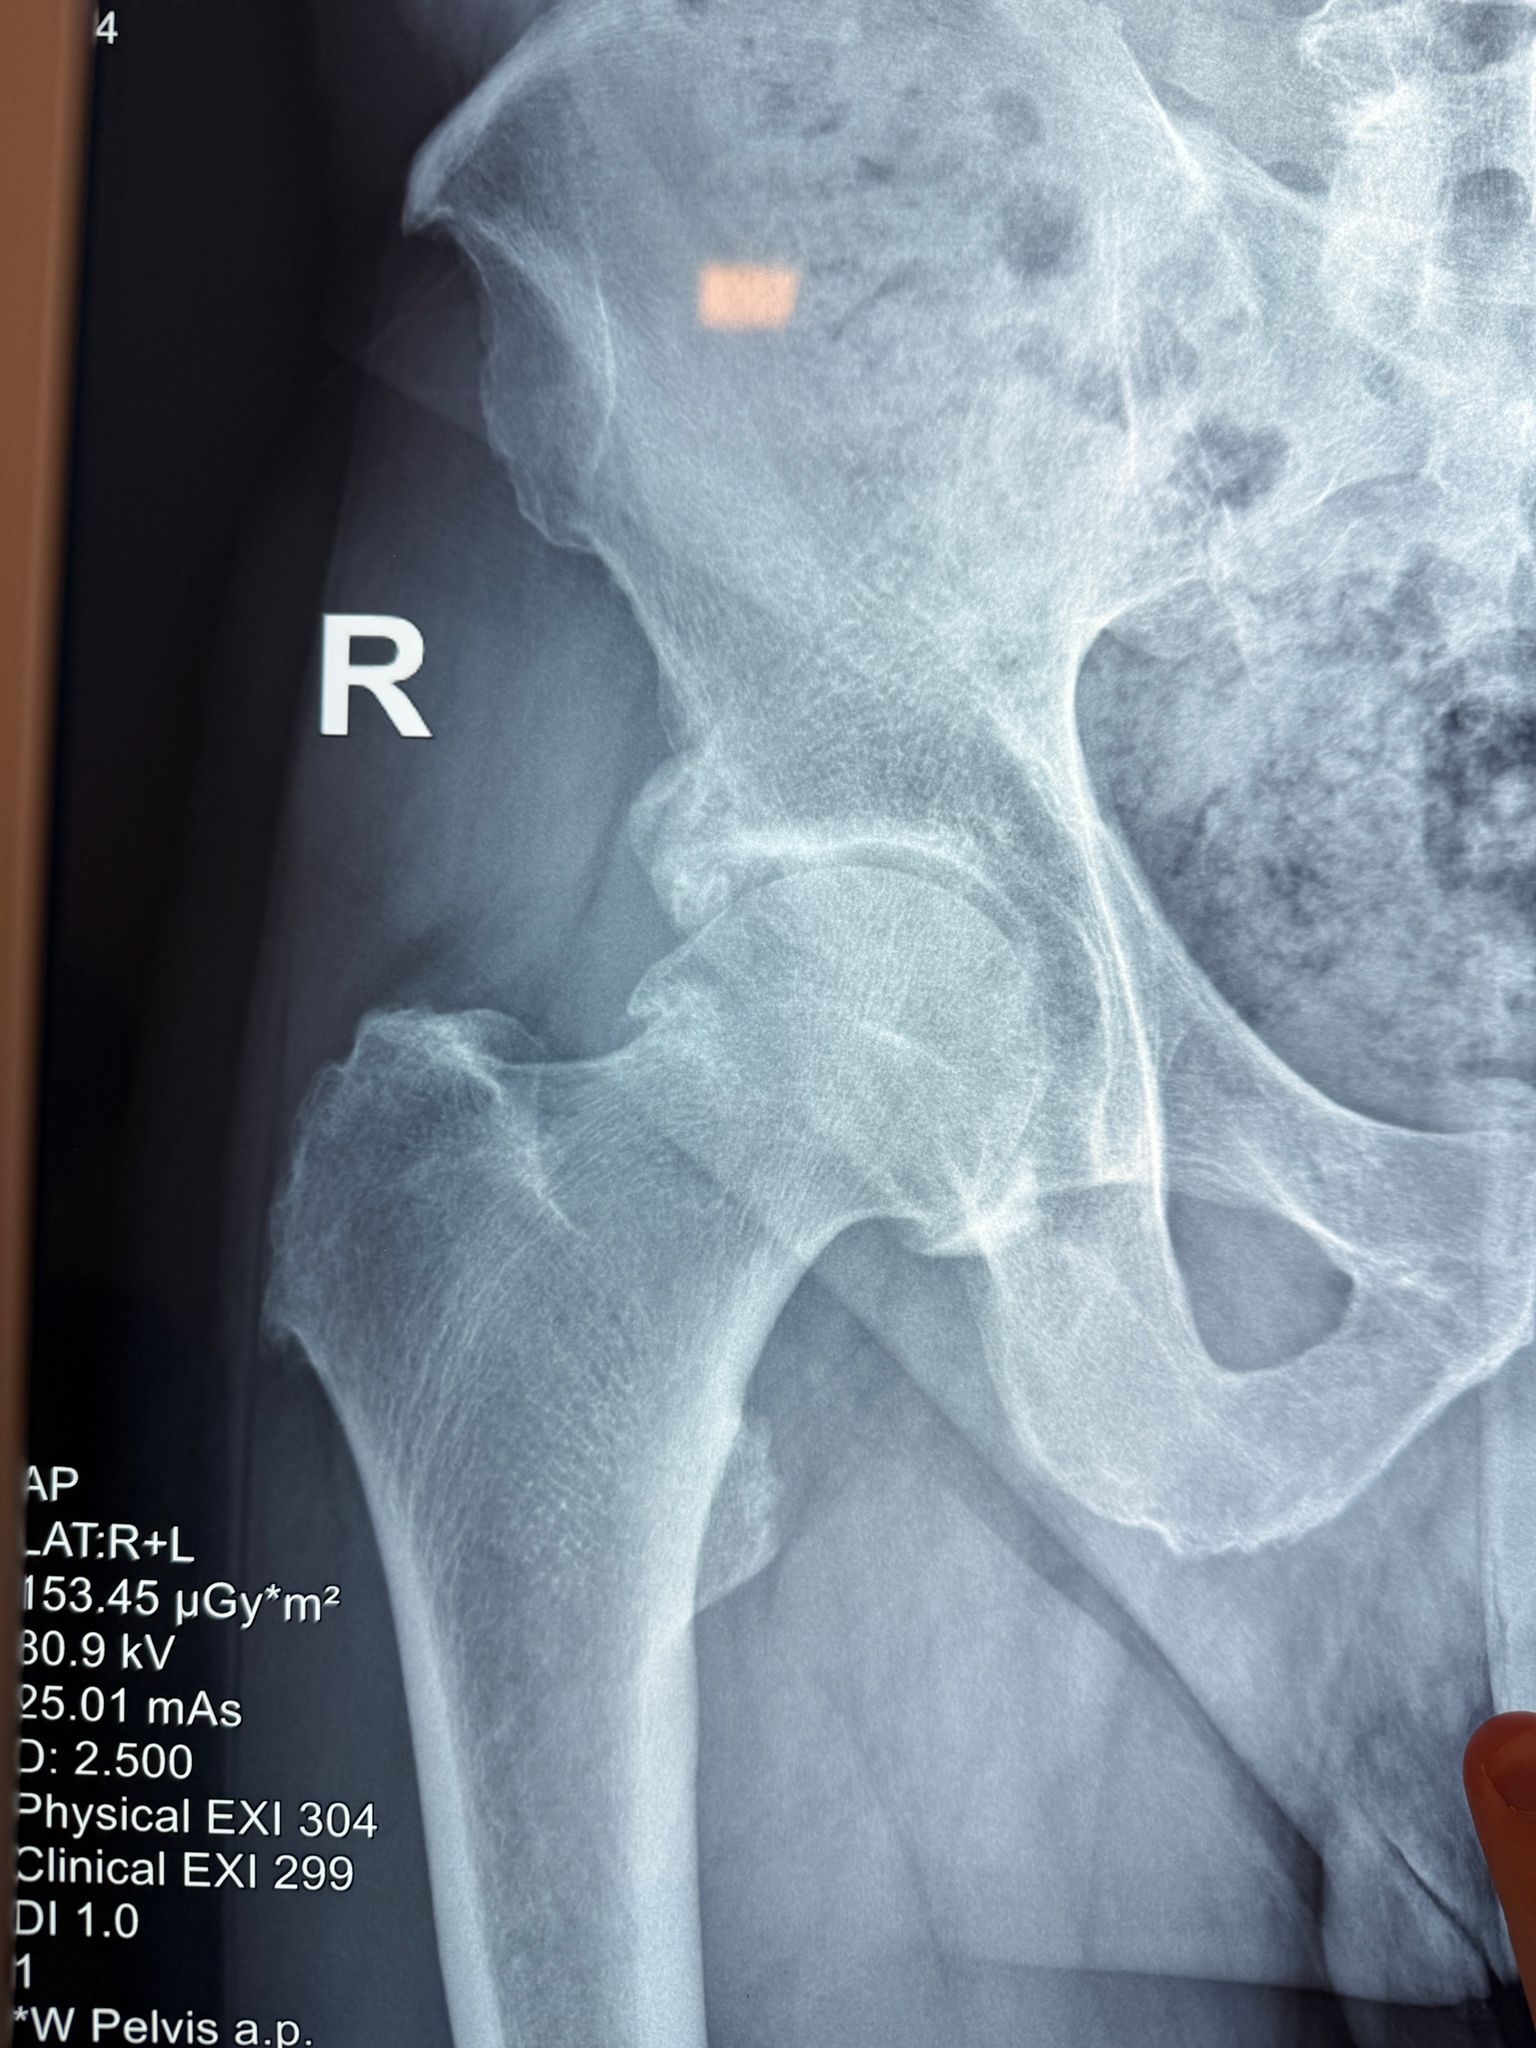

Imagini Clinice